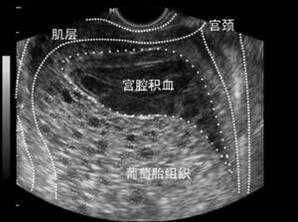

由于临床医生对于阴道出血、子宫增大且妊娠试验阳性的妇女多数怀疑为妊娠并发症,如先兆流产或稽留流产、异位妊娠,故详细确切的病史和全面的检查对妊娠滋养细胞疾病的正确诊断尤为重要。B超、MRI等影像学诊断也非常有价值,一般提示“宫腔蜂窝状改变”或“积雪征”。

图:B超提示完全性葡萄胎

多采用经阴道彩色多普勒超声检查,可检测到葡萄胎特征性超声表现。完全性葡萄胎的典型超声影像表现为:子宫明显大于孕周,宫内没有孕囊或胎心搏动,部分性葡萄胎有时可见胎儿或羊膜囊,但胎儿常合并畸形;侵润性葡萄胎通常表现为宫内1个或多个边界模糊的团块,含无回声区;绒毛膜癌表现为使子宫增大的不均质团块,这种不均质表现与坏死和出血区域对应,肿瘤可能会延伸到子宫旁组织;胎盘部位滋养细胞肿瘤表现为宫内胎儿可能存活,胎盘高回声团,团块通常侵及子宫肌壁。

(图:完全性葡萄胎超声图)